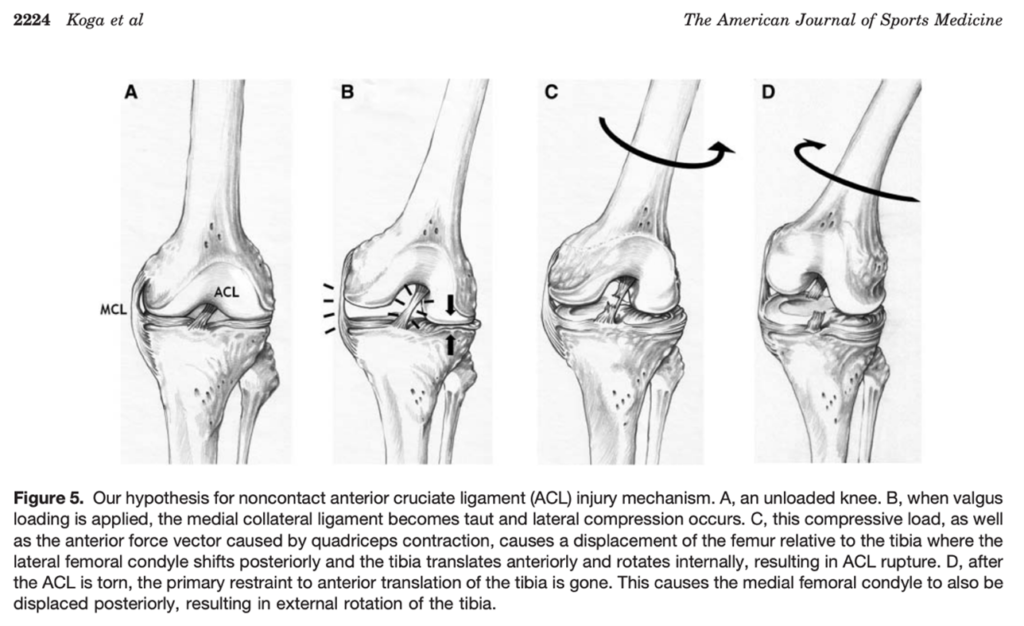

No caso de Murray, é possível identificar em vídeo a lesão com o joelho em valgo, que ocorre sem nenhum trauma direto. Em estudo retrospectivo que avaliou 1000 casos de lesões de LCA em atletas adolescentes, 67% das lesões no basquete também ocorreram sem contato direto, associadas à aterrisagem ou giro e mudança de direção (7). Este mecanismo de lesão do LCA no basquete também já foi discutido em uma série de 39 vídeos (8). Ainda com relação a biomecânica no momento da lesão, Koga et al (2010) evidenciou que após 40 milisegundos do contato inicial ao solo, ocorre um aumento da flexão (24º) e valgo (12º), acompanhados por uma rotação interna inicialmente (8º) seguida pela rotação externa (17º) com uma carga de 3,2 vezes o peso corporal (9) (Fig. 1 -3).

Fig. 3 – Reprodução da Fig. 5 de Koga H, et al. Mechanisms for noncontact anterior cruciate ligament injuries: knee joint kinematics in 10 injury situations from female team handball and basketball. Am J Sports Med. 2010

Fig. 3 – Reprodução da Fig. 5 de Koga H, et al. Mechanisms for noncontact anterior cruciate ligament injuries: knee joint kinematics in 10 injury situations from female team handball and basketball. Am J Sports Med. 2010